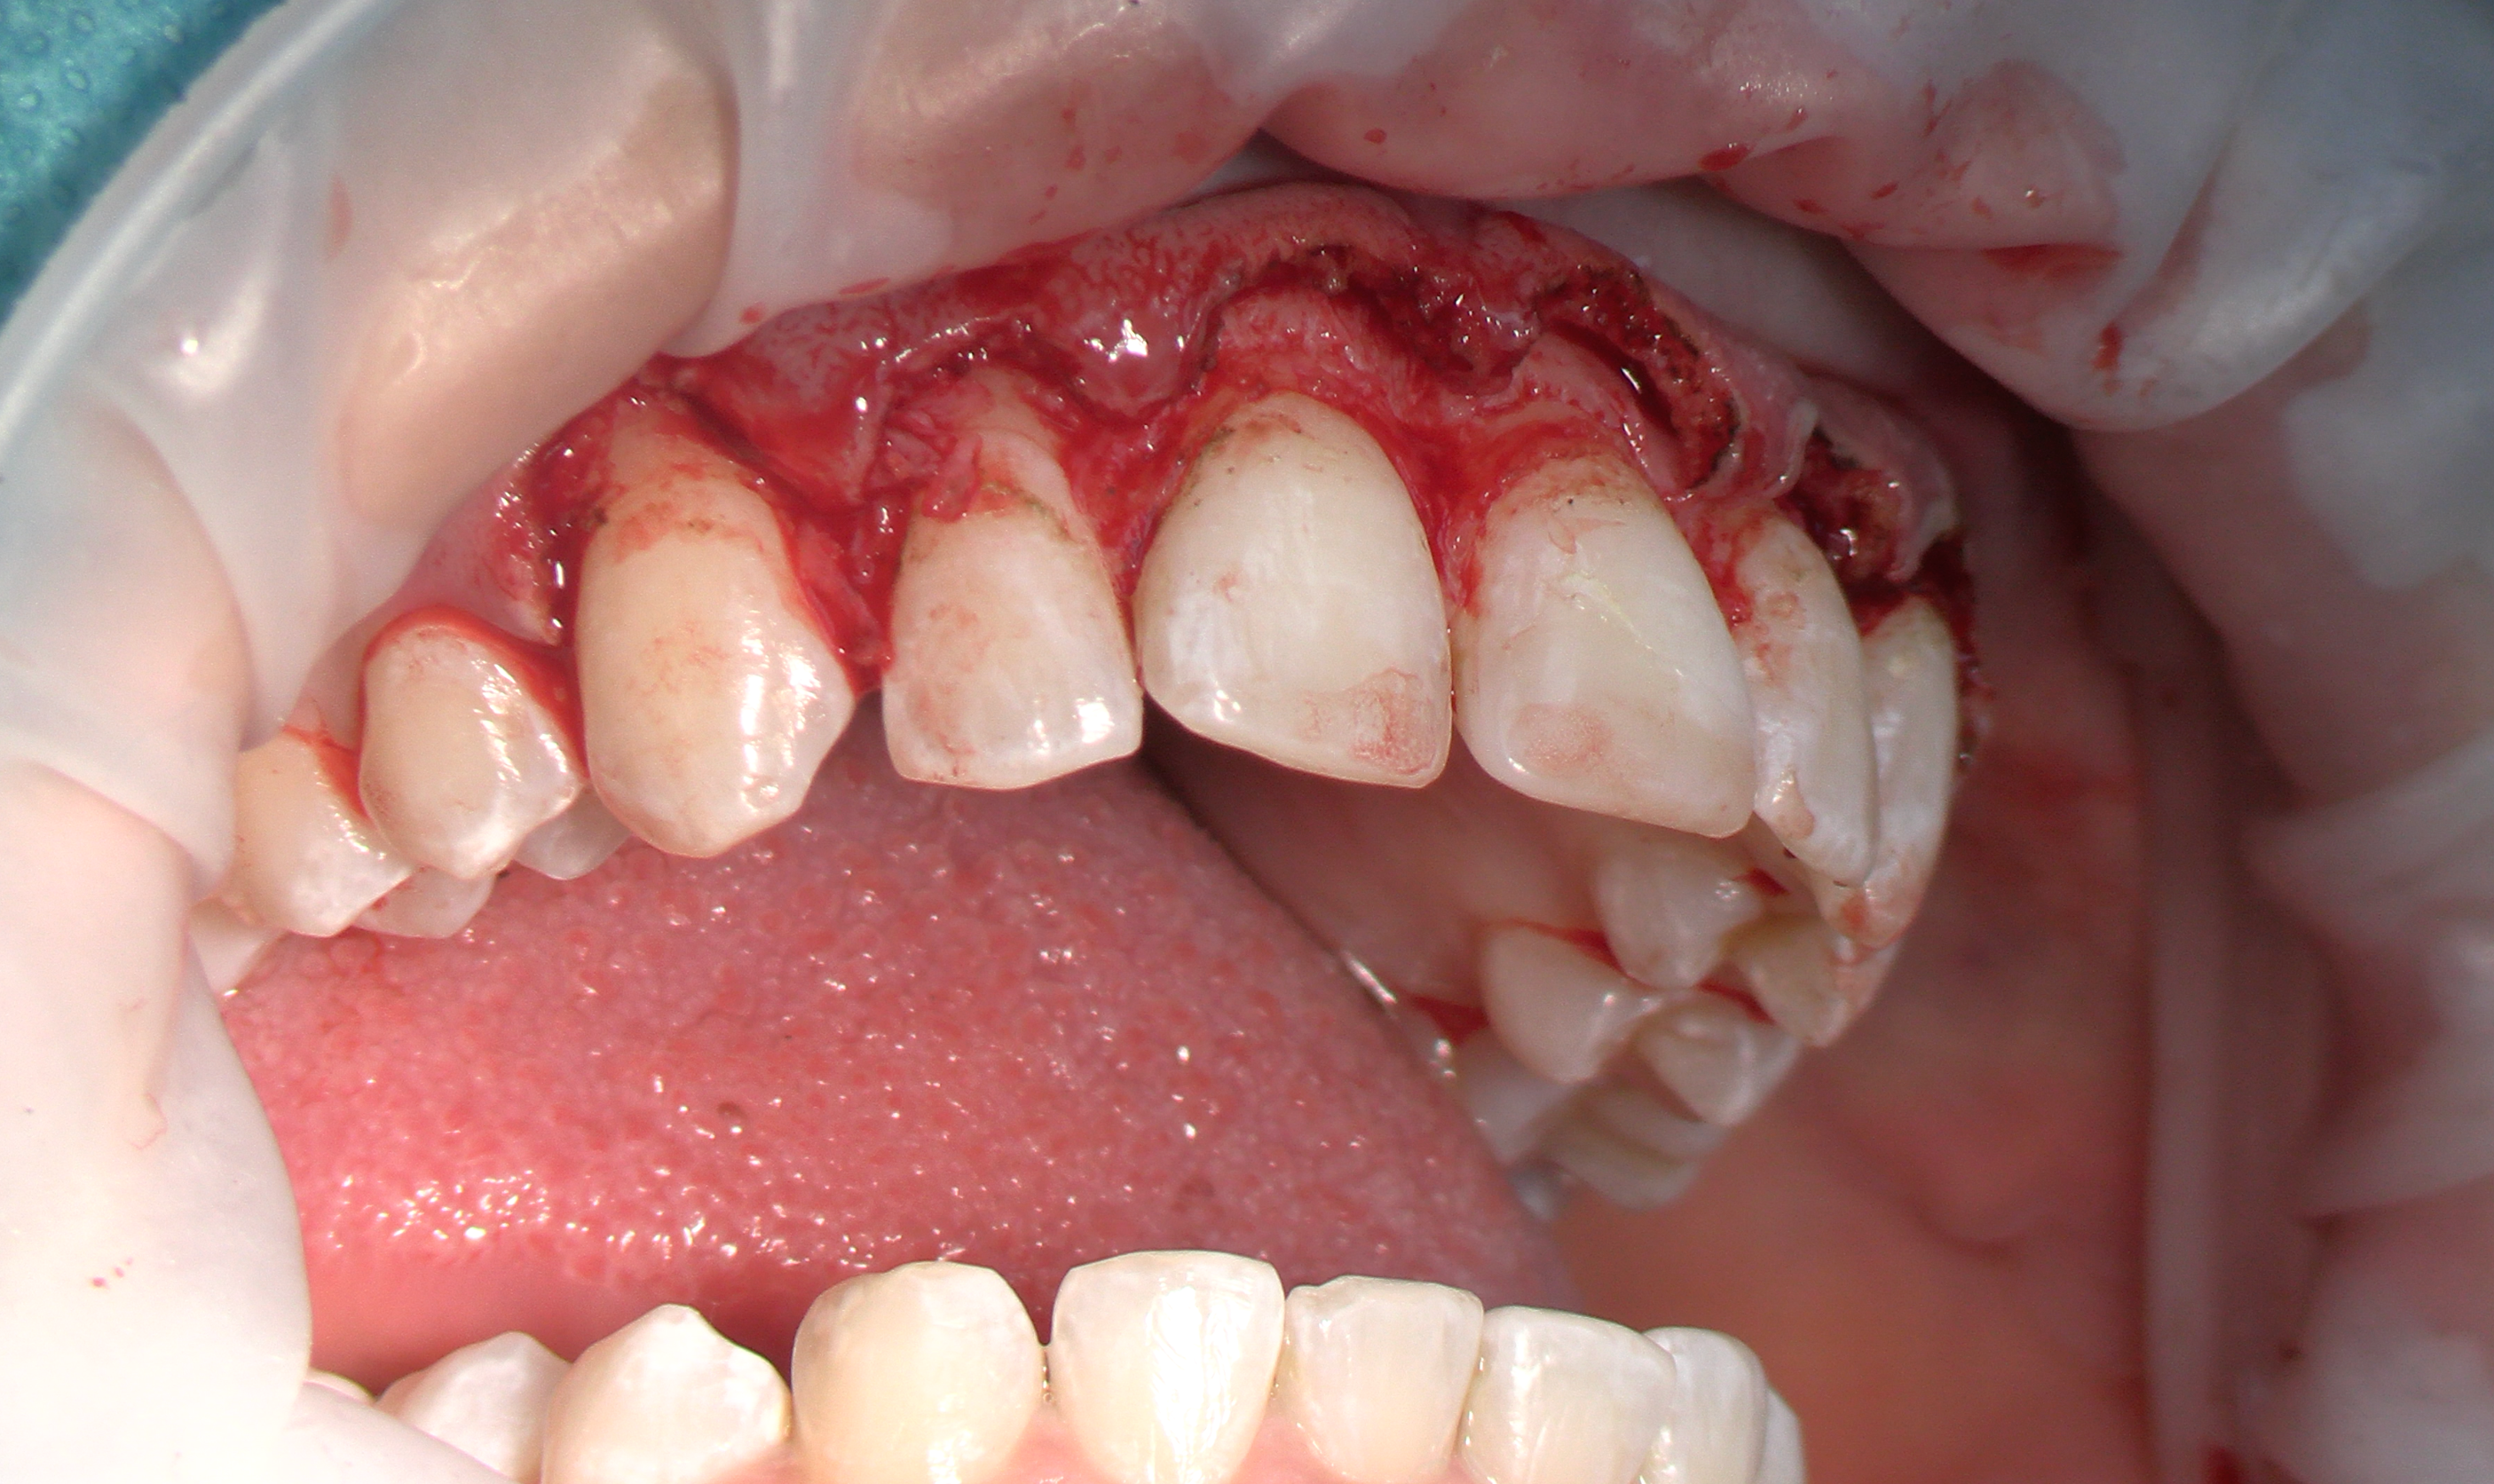

Exemples de planifications et de réalisations d'élongations coronaires du cas simple de gingivectomie, jusqu’à l’élongation coronaire avec ostéotomie dans le cadre de grosses réhabilitations.